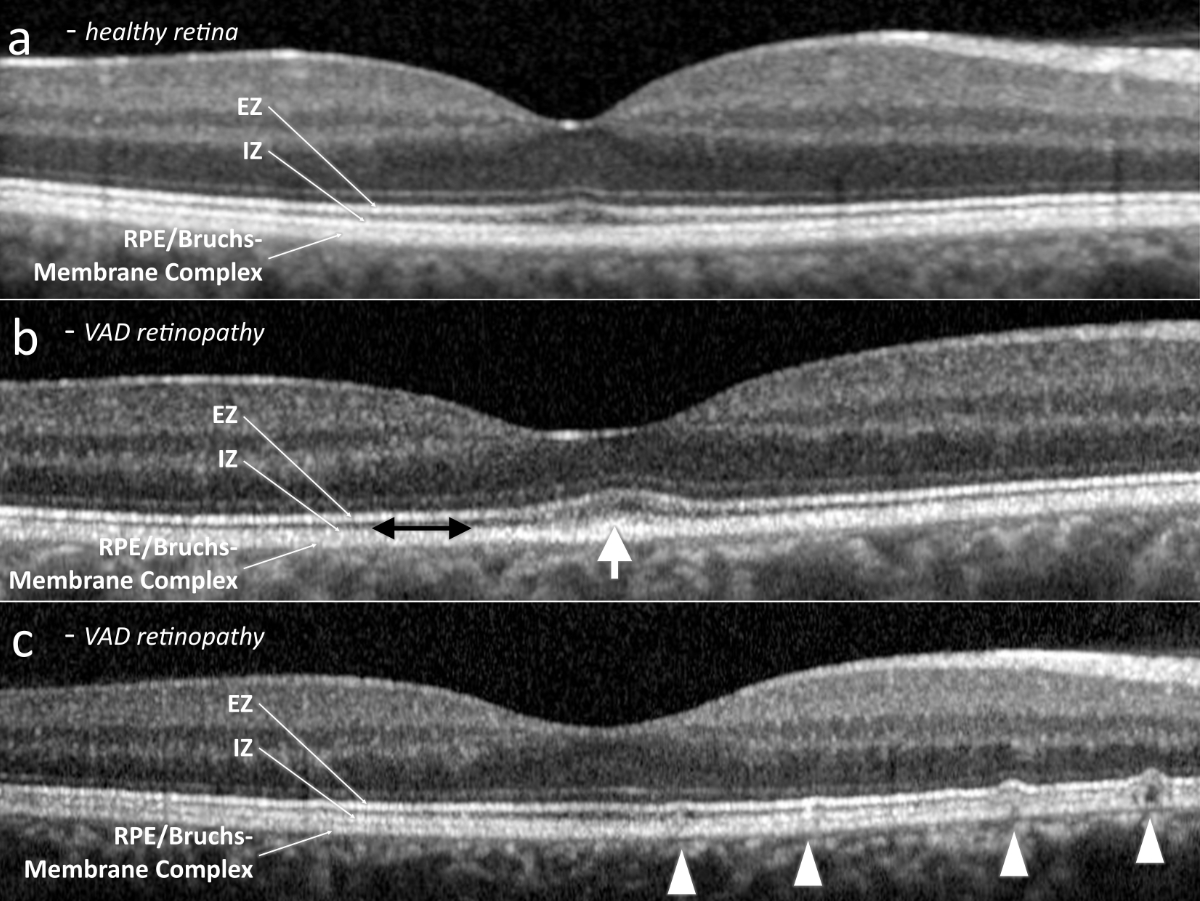

All patients had visible alterations of the outer retinal layers shown by optical coherence tomography (figure 2). These ranged from minimal irregularity to a complete absence of the interdigitation zone or an altered ellipsoid zone. Patients also varied in the presence of subretinal drusenoid deposits. Fundus autofluorescence showed varying degrees of speckled patches of hypofluorescence in four patients (the remaining patient did not undergo fundus autofluorescence imaging) (figure 3). Electroretinogram findings varied widely from abnormal oscillatory potentials to reduced or delayed mixed rod–cone a- and/or b-waves to non-recordable rod responses (for details see table 2). Three patients had dark adaptation tested, and all findings were pathological (figure 4). Two patients displayed abnormally slowed dark adaptation with reduced sensitivity throughout the 30-minute testing period, while the other patient exhibited no reproducible change in sensitivity over the test duration. In terms of associated systemic history, three patients underwent bariatric surgery (all gastric bypasses) three, seven, and nine years prior to diagnosis of vitamin A deficiency retinopathy, respectively. One patient had a small bowel resection 10 years prior and had been on octreotide treatment for eight years due to a neuroendocrine tumour. Another patient had a history of cystic fibrosis; ileum and jejunum resections 12 and four years prior, respectively; lung transplantation; and severe hepatopathy of mixed origin, possibly secondary to polymedication.

Figure 2Subfoveal optical coherence tomography. (a) Exemplary healthy retina. (b) Vitamin A deficiency retinopathy, presenting abnormal outer retinal foveal hyperreflectivity (white arrow) and a reduced interdigitation zone (black double arrow). (c) Vitamin A deficiency retinopathy, revealing subretinal drusenoid deposits (arrow heads). EZ: ellipsoid zone; ONL: outer nuclear layer; RPE: retinal pigment epithelium.